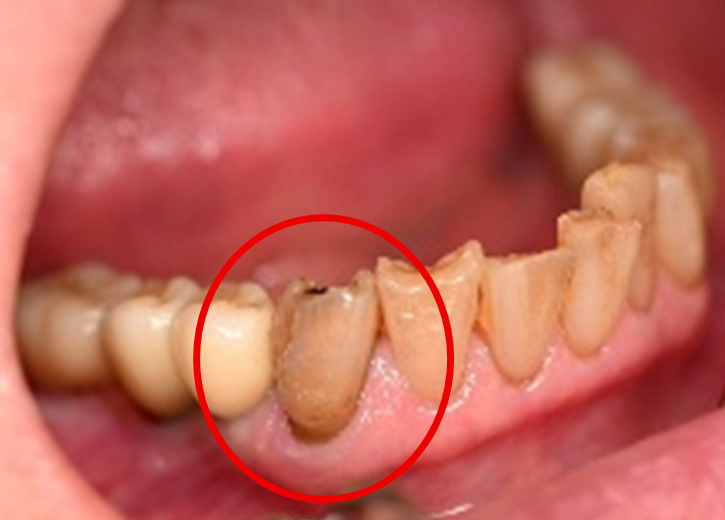

女性Yさん 60代(オールセラミック冠)

主訴

以前治療した右下の犬歯が、虫歯になり色が変わってきているので、治したい。

治療内容

根管治療をし、オールセラミック冠を被せました。

所感

神経が取り除かれ、歯自体が変色し、虫歯になっていました。根管治療をし、ファイバーコアを入れ、オールセラミック冠を被せました。

オールセラミック冠(失活歯)1本:¥104,500(税込)

Before

After